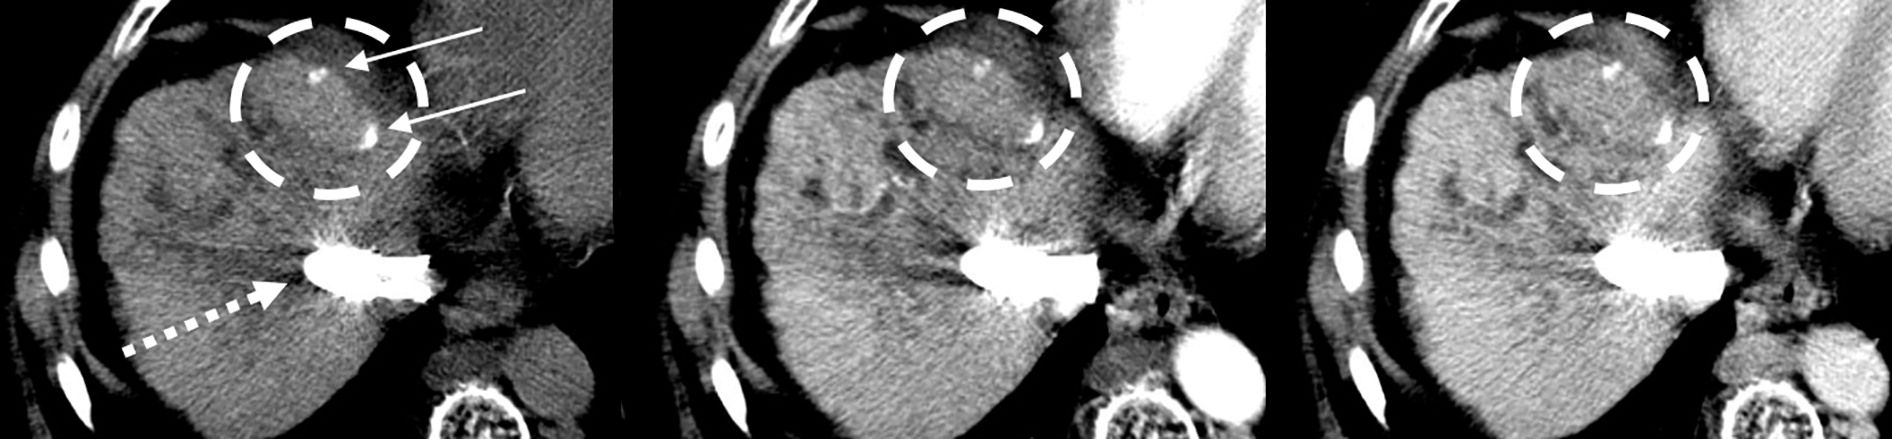

Dual-energy CT is a relatively new CT technology that can characterize tissue beyond conventional CT, and combining radiomic features from DECT exams with deep-learning algorithms shows promise for the diagnosis of rare HCC subtypes, according to Li and colleagues.

To assess DECT's performance for this indication, the team conducted a study that included 262 patients with histopathologically confirmed HCC who underwent contrast-enhanced DECT between June 2019 and June 2022. The patients were recruited from three hospitals and divided into two different data sets for the deep-learning model the team developed; patients from center 1 were included in a training set (n = 146) and an internal data set (n = 35), and those from centers 2 and 3 in an external test data set (n = 81). The investigators compared the deep-learning model's performance to a clinical-radiologic model using the area under the receiver operating characteristic curve (AUC) measure.

The deep-learning model better predicted the presence of the aggressive macrotrabecular-massive subtype of HCC than did the clinical-radiologic model, the group found. Its sensitivity across all data sets was comparable and its specificity was especially higher in the external test set.